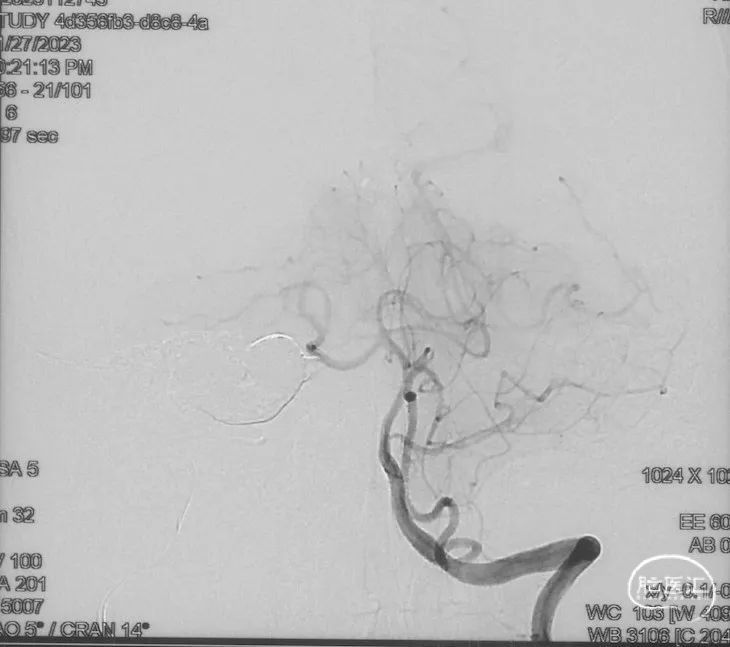

Echelon-10微导管在ASAHI 0.010微导丝导引下经右侧脑膜中动脉分支超选至瘘口,可见瘘口口径大,微导管直接越过瘘口,进入引流静脉起始部。

Marathon微导管在ASAHI 0.010微导丝导引下经右侧脑膜中动脉分支超选至瘘口近端。

经Marathon微导管手推造影明确微导管位于瘘口动脉端,Echelon-10微导管位于瘘口引流静脉起始端处扩张的静脉球内。

由于瘘口流量大,为了防止栓塞材料过度弥散,并逃逸至深静脉,首先通过Echelon-10微导管向静脉球内填入Feng 12/40、Feng 10/30两枚弹簧圈,限制后续液态栓塞材料仅在静脉起始部弥散。

随后回撤Echelon-10微导管,并通过Echelon-10微导管和Marathon微导管交替注入Onyx-34、Onyx-18,此时可见Onyx首先被血流冲至静脉球内,但被弹簧圈篮筐限制,并在瘘口范围内弥散。

通过“注射-停顿-再注射”,Onyx进一步在瘘口及供血动脉段和引流静脉起始部弥散满意

造影显示瘘口不显影,无静脉早显。